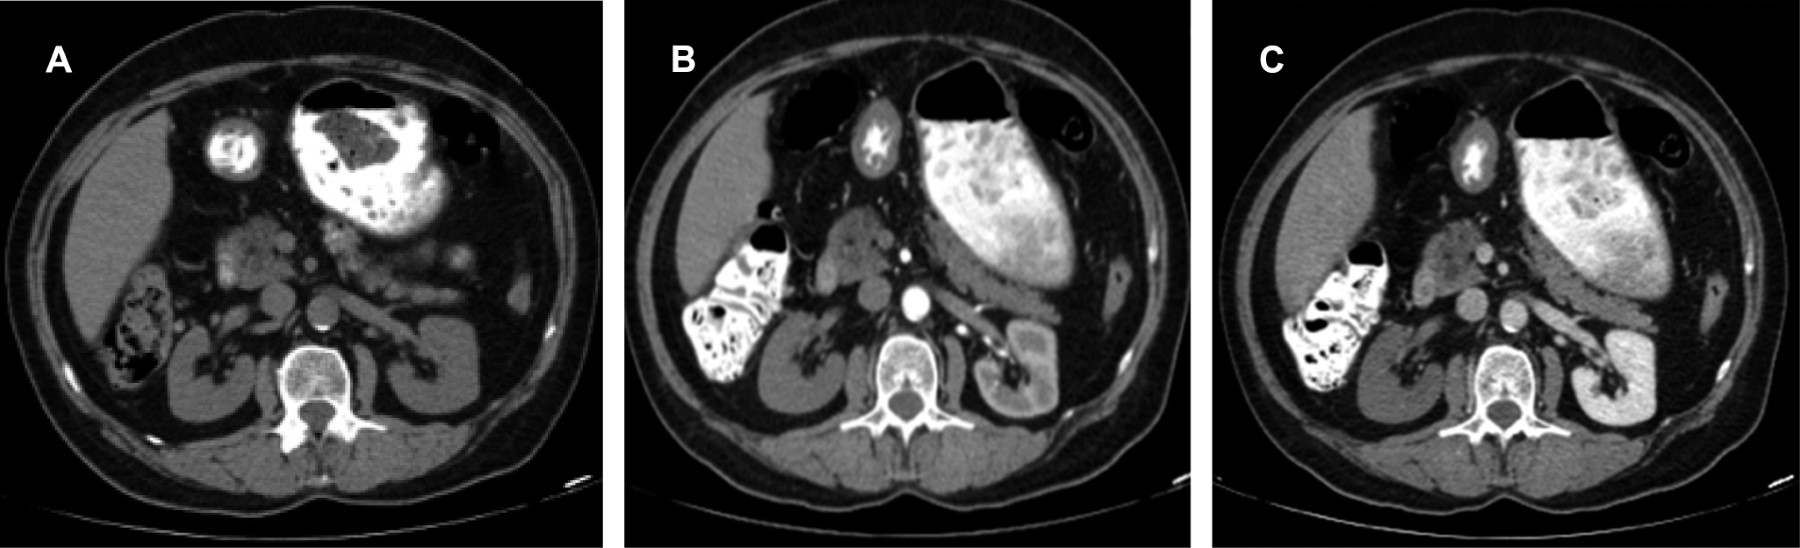

En fase arterial, la angiotomografía evidencia amputación de arteria renal derecha desde su origen con la consecuente ausencia de fase nefrográfica (Figuras 1 y 2).

La angiografía es el estudio de elección y es positiva en 100% de los casos, seguida de la angiotomografía, la cual es actualmente el estudio de elección por la mayor disponibilidad y por ser menos invasiva para el paciente. Los datos tomográficos de diagnóstico son: riñón hipodenso en fase arterial consistente con dato de hipoperfusión renal, aspecto de masa y ausencia de realce en forma de cuña.1,4 La morfología cuneiforme puede traducir isquemia parcial. La correlación con la cínica y laboratorios permite realizar el diagnóstico diferencial con pielonefritis. De manera oportuna permitirá la intervención temprana y adecuada para preservar la viabilidad renal y deberá considerarse en pacientes con factores de riesgo aun con cuadro clínico inespecífico, ya que el estudio tomográfico simple es inservible en este padecimiento.